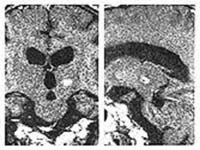

³úµ¿Á¤¸Æ

񃀁

³ú

±íÀº °÷¿¡ À§Ä¡ÇÏ¿© ³úÃâÇ÷À» ÀÏÀ¸Å² 17¼¼

¿©ÀÚȯÀÚÀÇ MRI ¹× ³úÇ÷°üÃÔ¿µ¼ú »çÁø.

³úÀÇ

±íÀº °÷¿¡ ³úµ¿Á¤¸Æ±âÇüÀÌ À§Ä¡ÇÏ¿© ¼ö¼úÀû

Ä¡·á°¡ ºÒ°¡´ÉÇÏ¿´À¸³ª °¨¸¶³ªÀÌÇÁ ½Ã¼ú

ÈÄ 24°³¿ù°¿¡ ¸ðµÎ ¿ÏÄ¡µÇ¾ú´Ù

°æ·ÃÀ»

ÁÖ¼Ò·Î ÀÔ¿øÇÑ È¯ÀÚÀÇ MRI ¹× ³úÇ÷°üÃÔ¿µ¼ú

»çÁø.

µ¿Á¤¸Æ±âÇüÀÇ

Å©±â°¡ Ä¿¼ ¼ö¼úÀÇ À§Ç輺ÀÌ ³ô¾Æ °¨¸¶³ªÀÌÇÁ¸¦

°èȹÇÏ¿´´Ù. º´º¯ÀÇ Å©±â°¡ Ä¿¼ °¨¸¶³ªÀÌÇÁ

¹æ»ç¼±¼ö¼úÀ» ¸îÂ÷·Ê¿¡ ³ª´©¾î¼ ½ÃÇàÇÏ·Á

ÇÏ¿´À¸³ª ÇÑÂ÷·ÊÀÇ °¨¸¶³ªÀÌÇÁ ½Ã¼ú ÈÄ

24°³¿ù° ¸ðµÎ ¿ÏÄ¡µÇ¾ú´Ù.

º´º¯ÀÇ

Å©±â°¡ Å« µ¿Á¤¸Æ±âÇüÀÇ °æ¿ì °¨¸¶³ªÀÌÇÁ

¹æ»ç¼±¼ö¼úÀ» ¸îÂ÷·Ê¿¡ ³ª´©¾î¼ ½ÃÇàÇÏ¿©¾ß

Çϳª ÀϺΠȯÀÚÀÇ °æ¿ì ÇÑÂ÷·ÊÀÇ °¨¸¶³ªÀÌÇÁ

½Ã¼ú·Îµµ ¿ÏÄ¡¸¦ º¸¿´´Ù